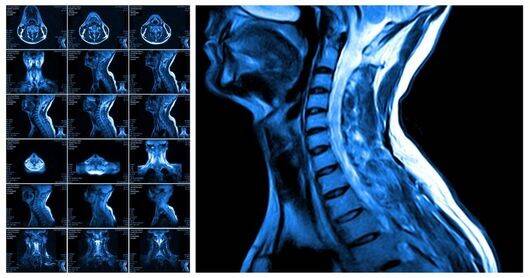

c) De MRI-scan (Magnetic Resonance Imaging– magneetscan)

Een MRI-scan levert beelden die vergelijkbaar zijn met de CT-scan. Het voordeel : in plaats van X-stralen worden hier magneetvelden en radiogolven gebruikt.

Het nadeel: een MR is duurder en duurt langer.

Waartoe dient het?

De MRI-scan dient om beelden te maken van hersenen, spieren, pezen, gewrichten, bloedvaten, tussenwervelschijven enz ….

Wordt veel gebruikt om hersentumoren op te sporen

Hoe verloopt het?

De verpleegkundige brengt de patiënt in een bepaalde houding op de tafel van het MRI-toestel.

Die tafel schuift door een tunnel met een sterke magneet. Het maken van de beelden gebeurt in meerdere sessies van enkele minuten.

Gedurende het onderzoek hoort men regelmatig kloppende geluiden. Dit is het moment waarop de opnames gebeuren en u mag dan absoluut niet bewegen - (daarom worden hoofdtelefoon of oordopjes gegeven)

Het onderzoek kan 20 min. tot één uur in beslag nemen.

Omwille van de nauwe tunnel kunnen mensen met “extreme” obesitas dit onderzoek niet ondergaan.